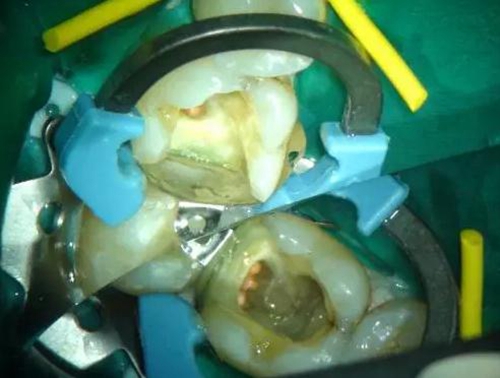

圖1 磨牙根管治療后進行核修復。Palodent V3節(jié)段型成型片、分牙器及楔子均已就位。成型片不會受到橡皮障的影響。可以看到遠中洞型底部成型片的良好貼合。窩洞已酸蝕及涂布粘接劑,牙面呈“潮濕”狀態(tài)。使用橡皮障更利于術區(qū)濕度控制。然后向窩洞注射SDR。要注意避免:粘接劑在根管口堆積。SDR注射針頭可以探入根管口。雖然SDR的固化深度是4mm,但是建議現(xiàn)在根管口及髓底涂布薄層SDR并固化。此處位置太深,光固化燈可能光強不夠。然后再疊加SDR,直至低于洞緣2-3mm。

圖2向窩洞內注射SDR。該病例中,顯微鏡使用黃色濾鏡,防止SDR過早固化。